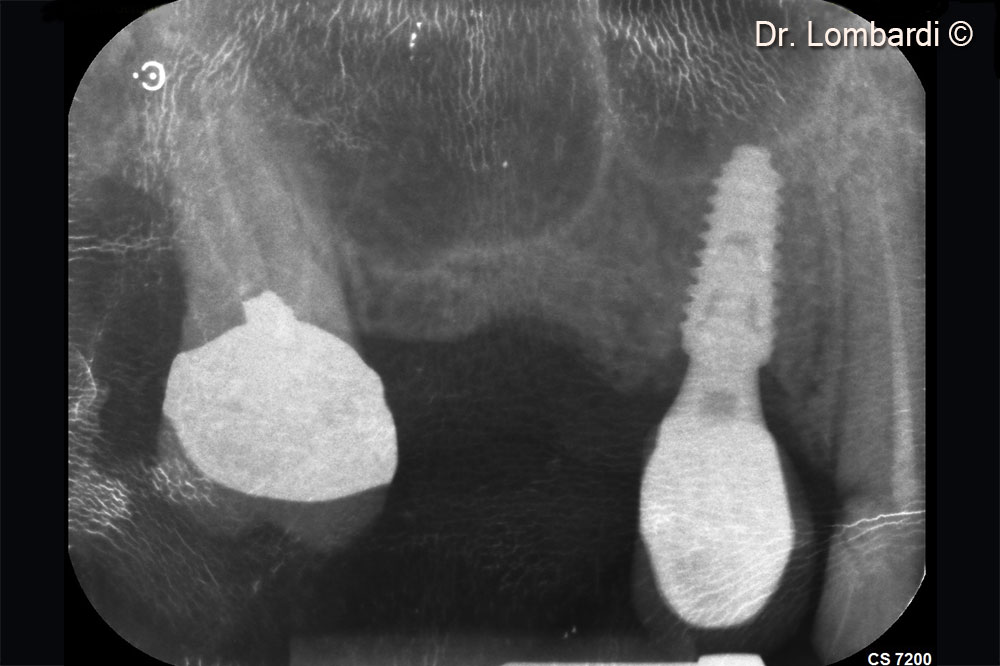

Initial situation

A male patient shows an atrophic maxilla. Bone augmentation is necessary before implant placement.

The bone crest needs to be augmented before implant placement